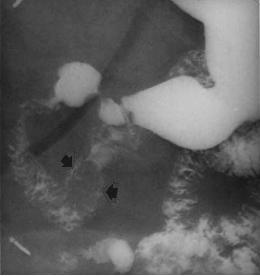

Image TOGD

baryte du cadre duodenal : : Aspect laculaire

ovalaire multilobulaire d'une tumeur leiomyoma de D3

( fleche noire ) |